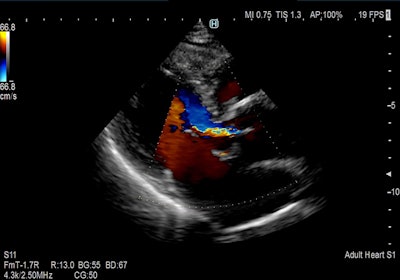

Philips Healthcare is launching a new version of the Epiq system, Epiq Elite, with two software packages, one for vascular imaging and another for ob/gyn applications. Epiq Elite includes an HD display for improved off-angle viewing; on the vascular imaging side, it features the xMatrix linear transducer as well as an upgraded 2D transducer; for ob/gyn applications, it features the V9-2 high-frequency pure wave transducer that allows clinicians to take detailed images as early as possible in pregnancy.

Sound Touch uses Ultra Wide Beam Tracking technology, which produces quantification metrics and visual displays of tissue stiffness. Ultra-Wideband Non-Linear (UWN+) contrast-enhanced imaging uses harmonic and fundamental signals to boost contrast and temporal resolution, while its iFusion tool supports the synthesis of routine B-mode images as well as fusion in CEUS and color/power modes. Mindray's V-flow displays hemodynamic information via speckle-tracking data taken from three plane waves.

The company is also introducing HERA (hyperaperture enhanced reconstruction architecture) W10, which features the Crystal Architecture tool. Crystal Architecture includes Samsung's CrystalBeam beamforming technology and CrystalLive processing engine, and features its S-Vue transducer. HERA W10 also includes ShadowHDR, which creates a shadow-suppressed image; MV-Flow, an alternative to color Doppler for visualizing slow-flow microvascularized structures; and LumiFlow, which offers 3D visualization blood flow images.